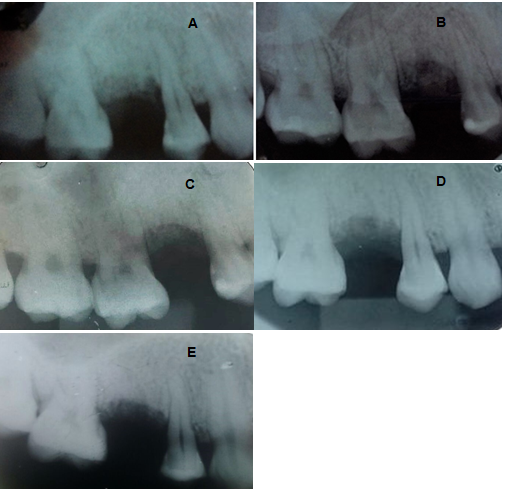

After extraction, no damage to the crystals was reported, and therefore, the preservation of the alveolar bone walls can be observed, starting the process of filling an alveolus with Bio-Gen - Bioteck®, or the biomaterial not inserted in the alveolus. And compressed with the aid of a calculator to ensure that all content is filled (Figure 4). Finally, a simple sample with shalon® 5-0 absorbable suture was performed using only the gingival tissue. In this case, the use of membranes was not necessary (Figure 5). The patient underwent periapical radiographs for follow-up, after which he remained with a control of 07, 30, 60 and 90 days (Figure 6).

Figure 6 (A) Immediate periapical radiography. (B) Periapical control radiograph 07 days after bone graft. (C) Periapical control radiograph 30 days after bone graft. (D) Periapical control radiograph 60 days after bone graft. (E) Control periapical radiograph 90 days after bone graft.

Result

Through the follow-up with periapical radiographs for 90 days, it was possible to evaluate that the new type of equine origin xenogen graft induces satisfactory bone neoformation and in a short period, it is possible to observe this new bone formation in the place where it was inserted. The equine xenograft, which makes it possible to install a subsequent dental implant with a good neoformation.

However, in a systematic literature review, the authors suggested that although minimally invasive techniques used in dental extraction decrease the dimensional changes of the alveolar store, they could not preclude the occurrence of physiological bone resorption after extraction.19.20 Smieszek-Wilczewska et al.,21 through research comparing the Bio-gen® equine graft with the Bio-oss® cattle, found that the former showed a statistically significant increase in radiological density compared to other biomaterials confirming the efficiency of the equine biomaterial.21

The 90-day radiographic follow-up showed that the new model of xenograft (equine) has relevant characteristics, good acceptance and rapid bone neoformation, which makes possible the installation of a posterior dental implant. With a good new formation. However, further research should be performed with computed tomography (CT) to better evaluate the efficacy of equine xenograft.